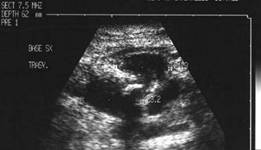

Scintigrafia si CT aceluiasi pacient, metastaza laterocervicala stg ce impinge traheea spre dr.

CT – aceeasi pacienta – agenezie lob stang